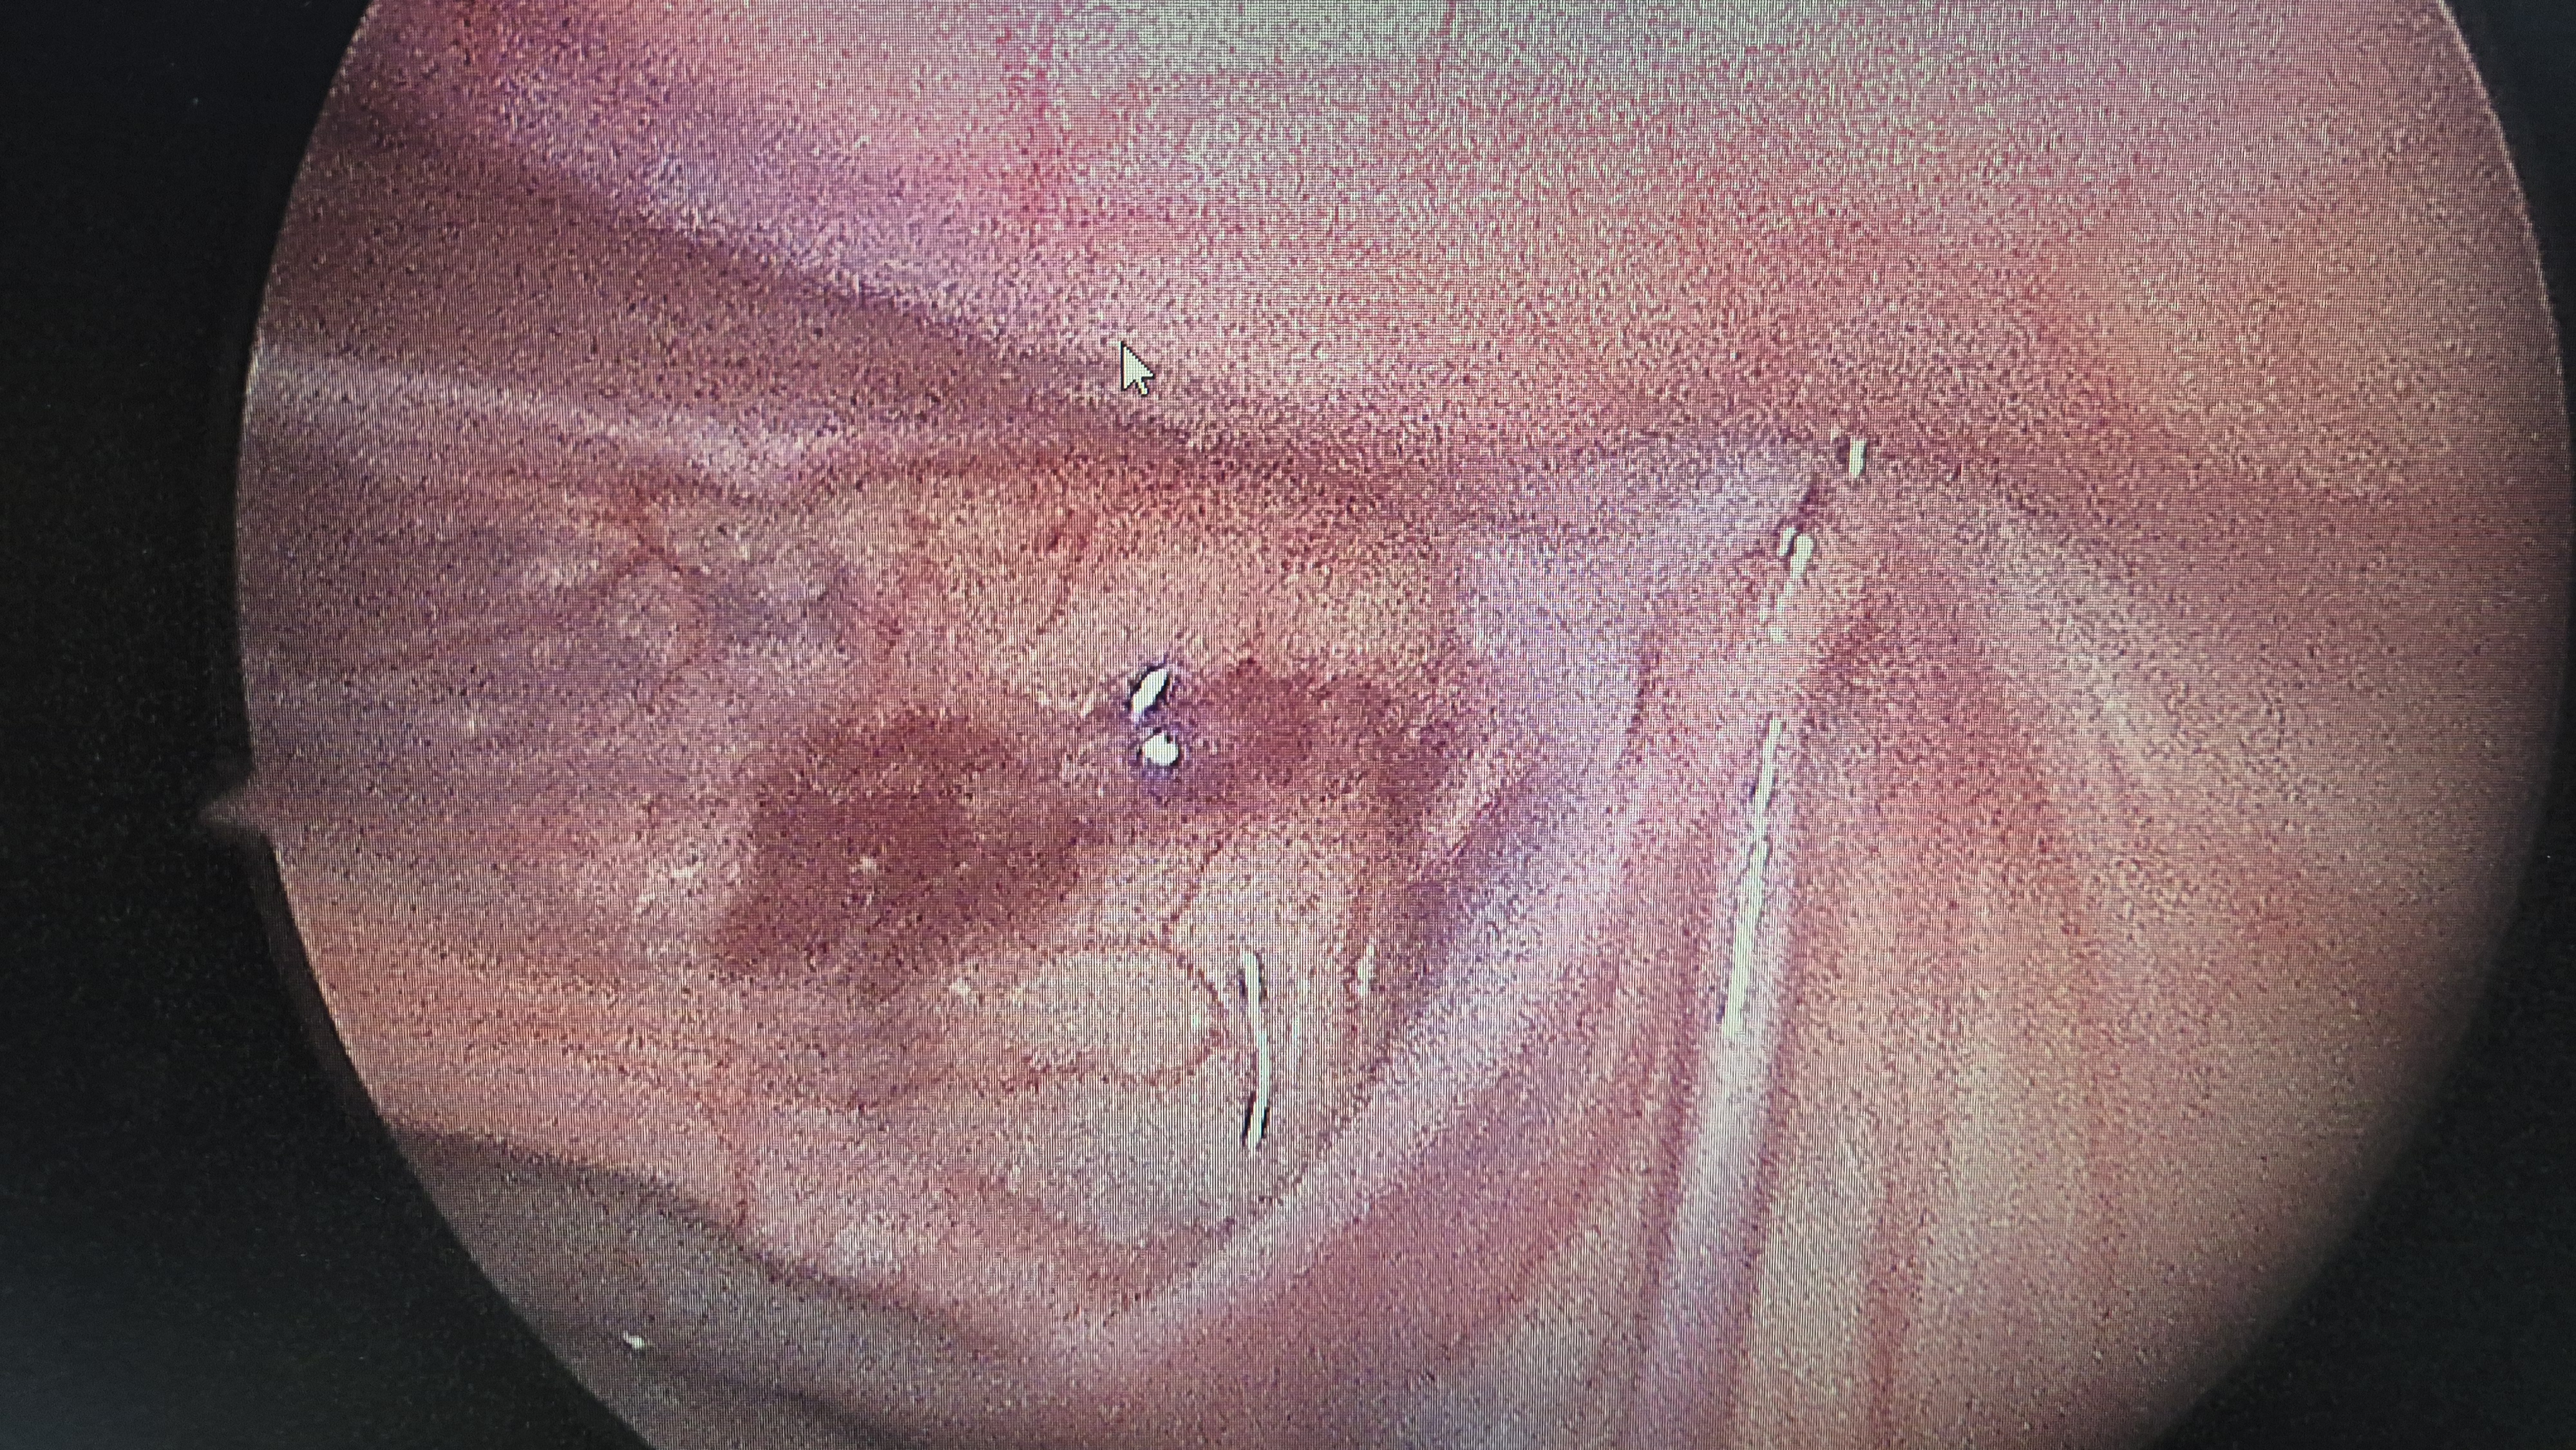

우측 서혜부 탈장.

교정후.